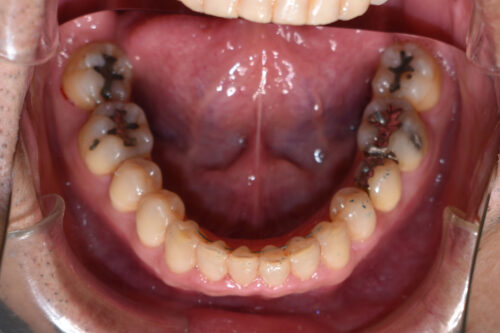

ワイヤー矯正治療12か月後です。

全額矯正治療 88万円、3~4週に一回来院

歯科矯正用アンカースクリュー(デュアル・トップオートスクリュー)上顎左右2本(25000円x2本分 提携医院にて)

ワイヤー期間 12か月, 16回来院

マウスピース型カスタムメイド矯正歯科治療を用いた矯正歯科治療装置を利用した矯正治療 3か月間 33000円、

本症例も

非抜歯矯正治療で終えるため

上顎左右臼歯部に

歯科矯正用アンカースクリュー(デュアル・トップオートスクリュー)を用い

下あごを オートローテーションさせ

また 上下の歯列全体を

後方へ移動させることで

歯を抜かなくても

口元の改善も行いました。